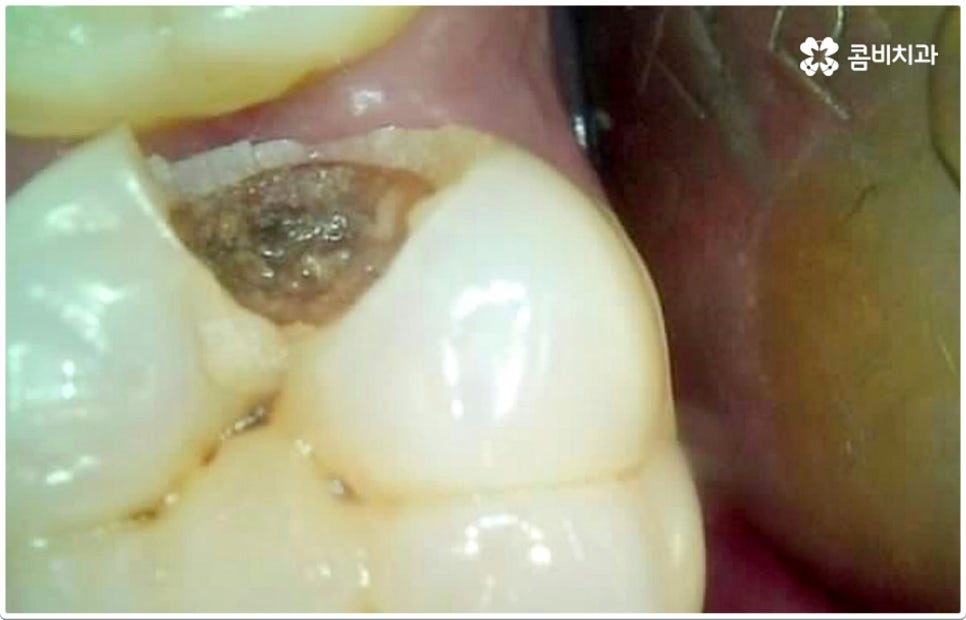

게다가 치아사이충치 는 두 치아의 인접면에 발생하여 한꺼번에 두 치아에 손상을 주기 때문에 보다 빠른 대처가 필요한데도 불구하고 말씀드린 것처럼 발견하기도 쉽지 않을 뿐더러 음식을 저작하는 치아의 교합면 (위아래 맞물리는 면) 에 생기는 충치가 아니기 때문에 수직으로 우식 부분까지 파고 내려가는 치과 충치 치료 기구들의 특성상 접근하기가 용이하지 않아 까다로운 진료에 속한다고 할 수 있어요. 특히 환자분들의 치아사이충치 발병 상황에 따라 치료 과정에서 부득이하게 삭제해야 하는 치아량이 생각보다 많아지는 케이스가 있을 수 있으므로 이에 대해 잘 알아두실 필요가 있습니다.

즉 환자분들이 느끼시기에는 육안으로 확인되는 우식 부위가 작은 것 같아도 안쪽으로 깊이 손상이 진행된 치아사이충치 케이스가 있을 수 있는데요. 이 때 맞닿은 치아 옆 면이 완전히 무너질 정도로 손상되었다면 이를 자연스럽게 복원하기 위해서는 레진으로 직접 때워주는 초기 충치 치료 방식을 사용하는 것은 적합하지 않고 인레이 치료를 통해 수복하는 방식이 필요하며, 레진 치료가 대부분 하루 만에 끝나는 비교적 간단한 것이라면 인레이 치료는 삭제한 부위에 딱 맞는 보철물을 만들어야 하기 때문에 시간도 더 오래 걸리고 비용도 커질 수 있으므로 환자분들께서 의료진과의 충분한 상담을 통해 자신의 상황이나 일련의 치아사이충치 치료 과정에 대해 그 필요성을 먼저 정확하게 이해한 후 치료를 받으시길 권유드리고 있어요. 만약 자체 기공소를 갖추고 있는 치과라면 환자분들에게 딱 맞는 보다 섬세하고 정교한 보철물 제작이 훨씬 빠르게 이뤄질 수 있다는 점에서 시간적인 부담을 줄여드릴 수 있으니 이 부분을 체크해 보시는 것도 좋을 거예요.